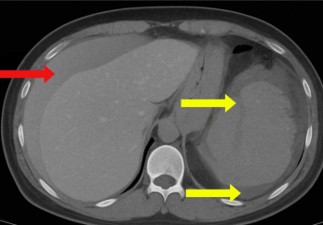

One day after the procedure, she visited the emergency department following three episodes of hematochezia and multiple episodes of near-syncope without loss of consciousness. She presented with intense abdominal discomfort, hypotension (BP=84/59 mmHg), and tachycardia (HR=110 bpm). A CT scan of the abdomen revealed a grade four splenic lesion in the middle third and free fluid in the splenic and perihepatic spaces (Figures 1 and 2).

Figure 1: Axial Computed Tomography (CT) scan showing splenic parenchymal blush with peritoneal extravasation (yellow arrows) and fluid in the perihepatic space (red arrow).